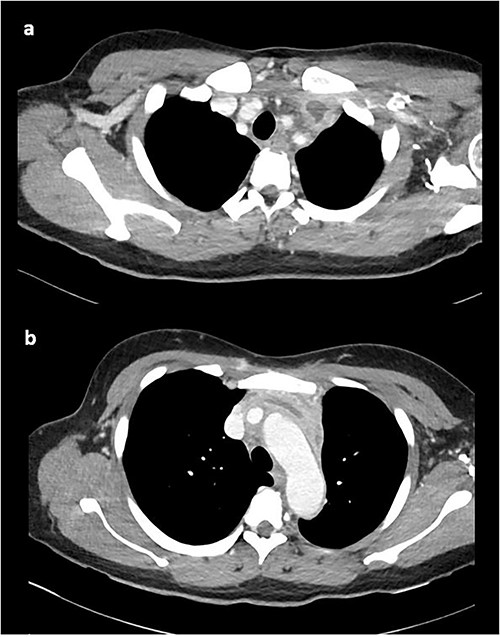

On repeat review of the CTPA, imaging was deemed atypical for acute aortic syndrome. A CT aortogram with delayed phase was performed, which demonstrated a 66-mm upper anterior mediastinal soft tissue density compressing the left brachiocephalic vein, as seen in Fig. 2.

CT chest with contrast demonstrating anterior mediastinal soft tissue density in the (a) upper chest and (b) lower chest.